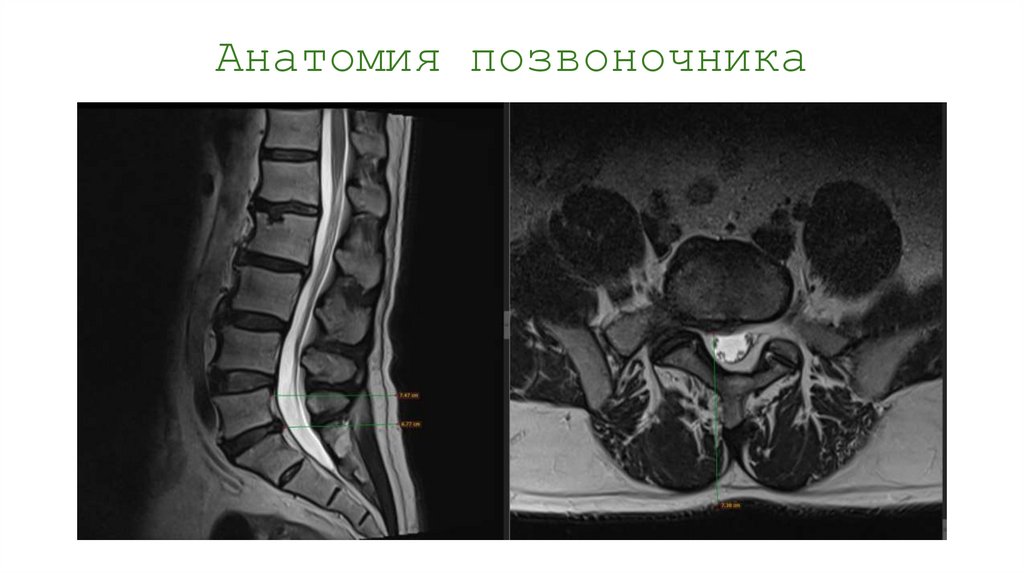

Анатомия позвоночника